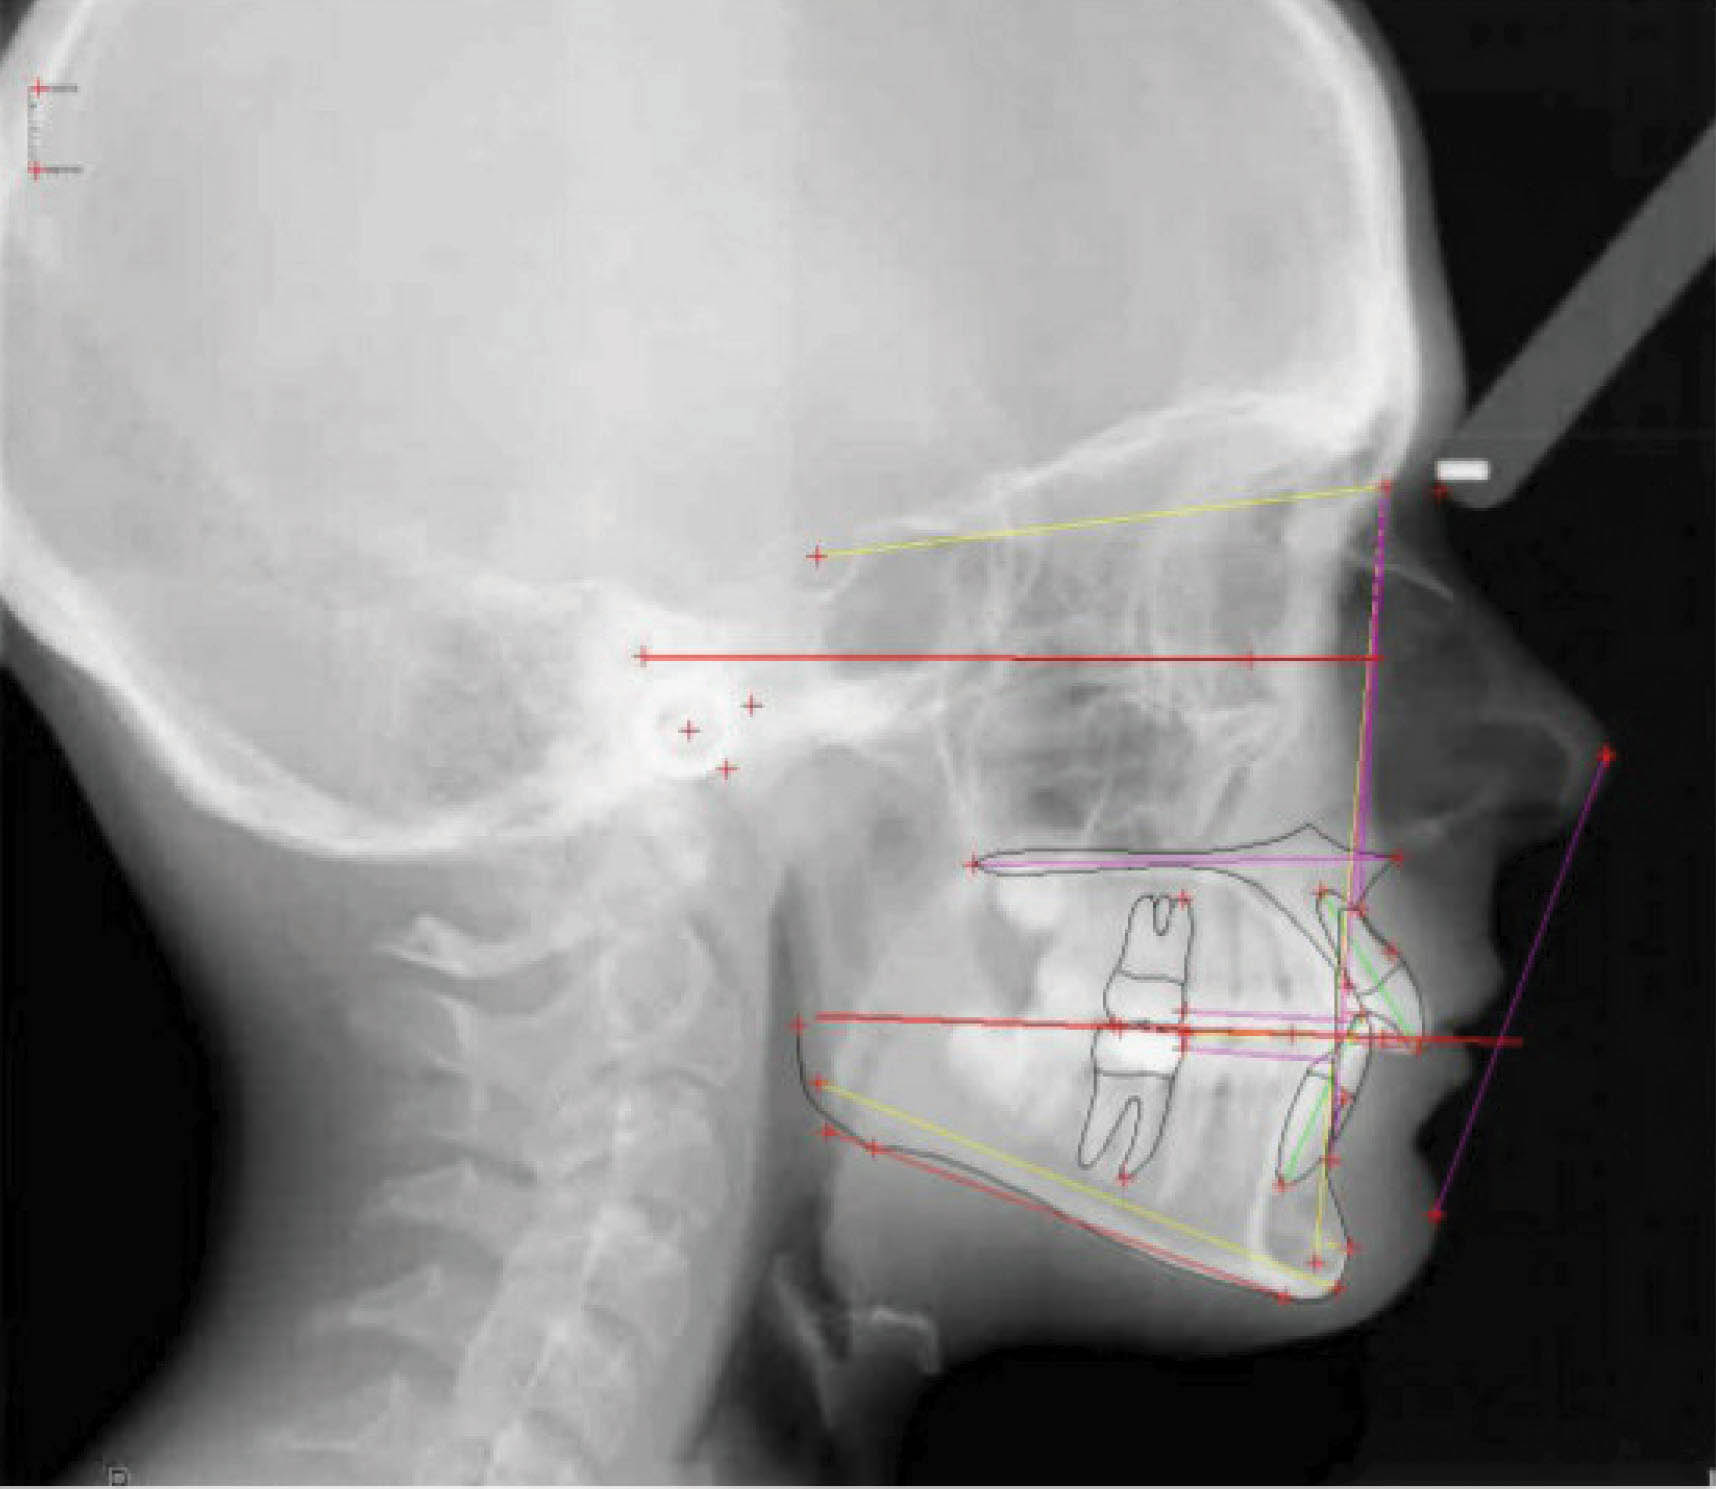

در شکلهای 109-۶ الی 111-۶ نتایج بدست آمده از درمان را ملاحظه میفرمایید. در سوپرایمپوز نمودن لترال سفالومتریها مشاهده میکنید که موقعیت مولر بالا ثابت مانده است درحالیکه هم رشد مندیبل و هم تغییرات دندانی را داریم. دیستاله نمودن دندانها در بیماران در حال رشد درمان خوبی میباشد.

شکل 109-6

شکل 110-6

شکل111-6